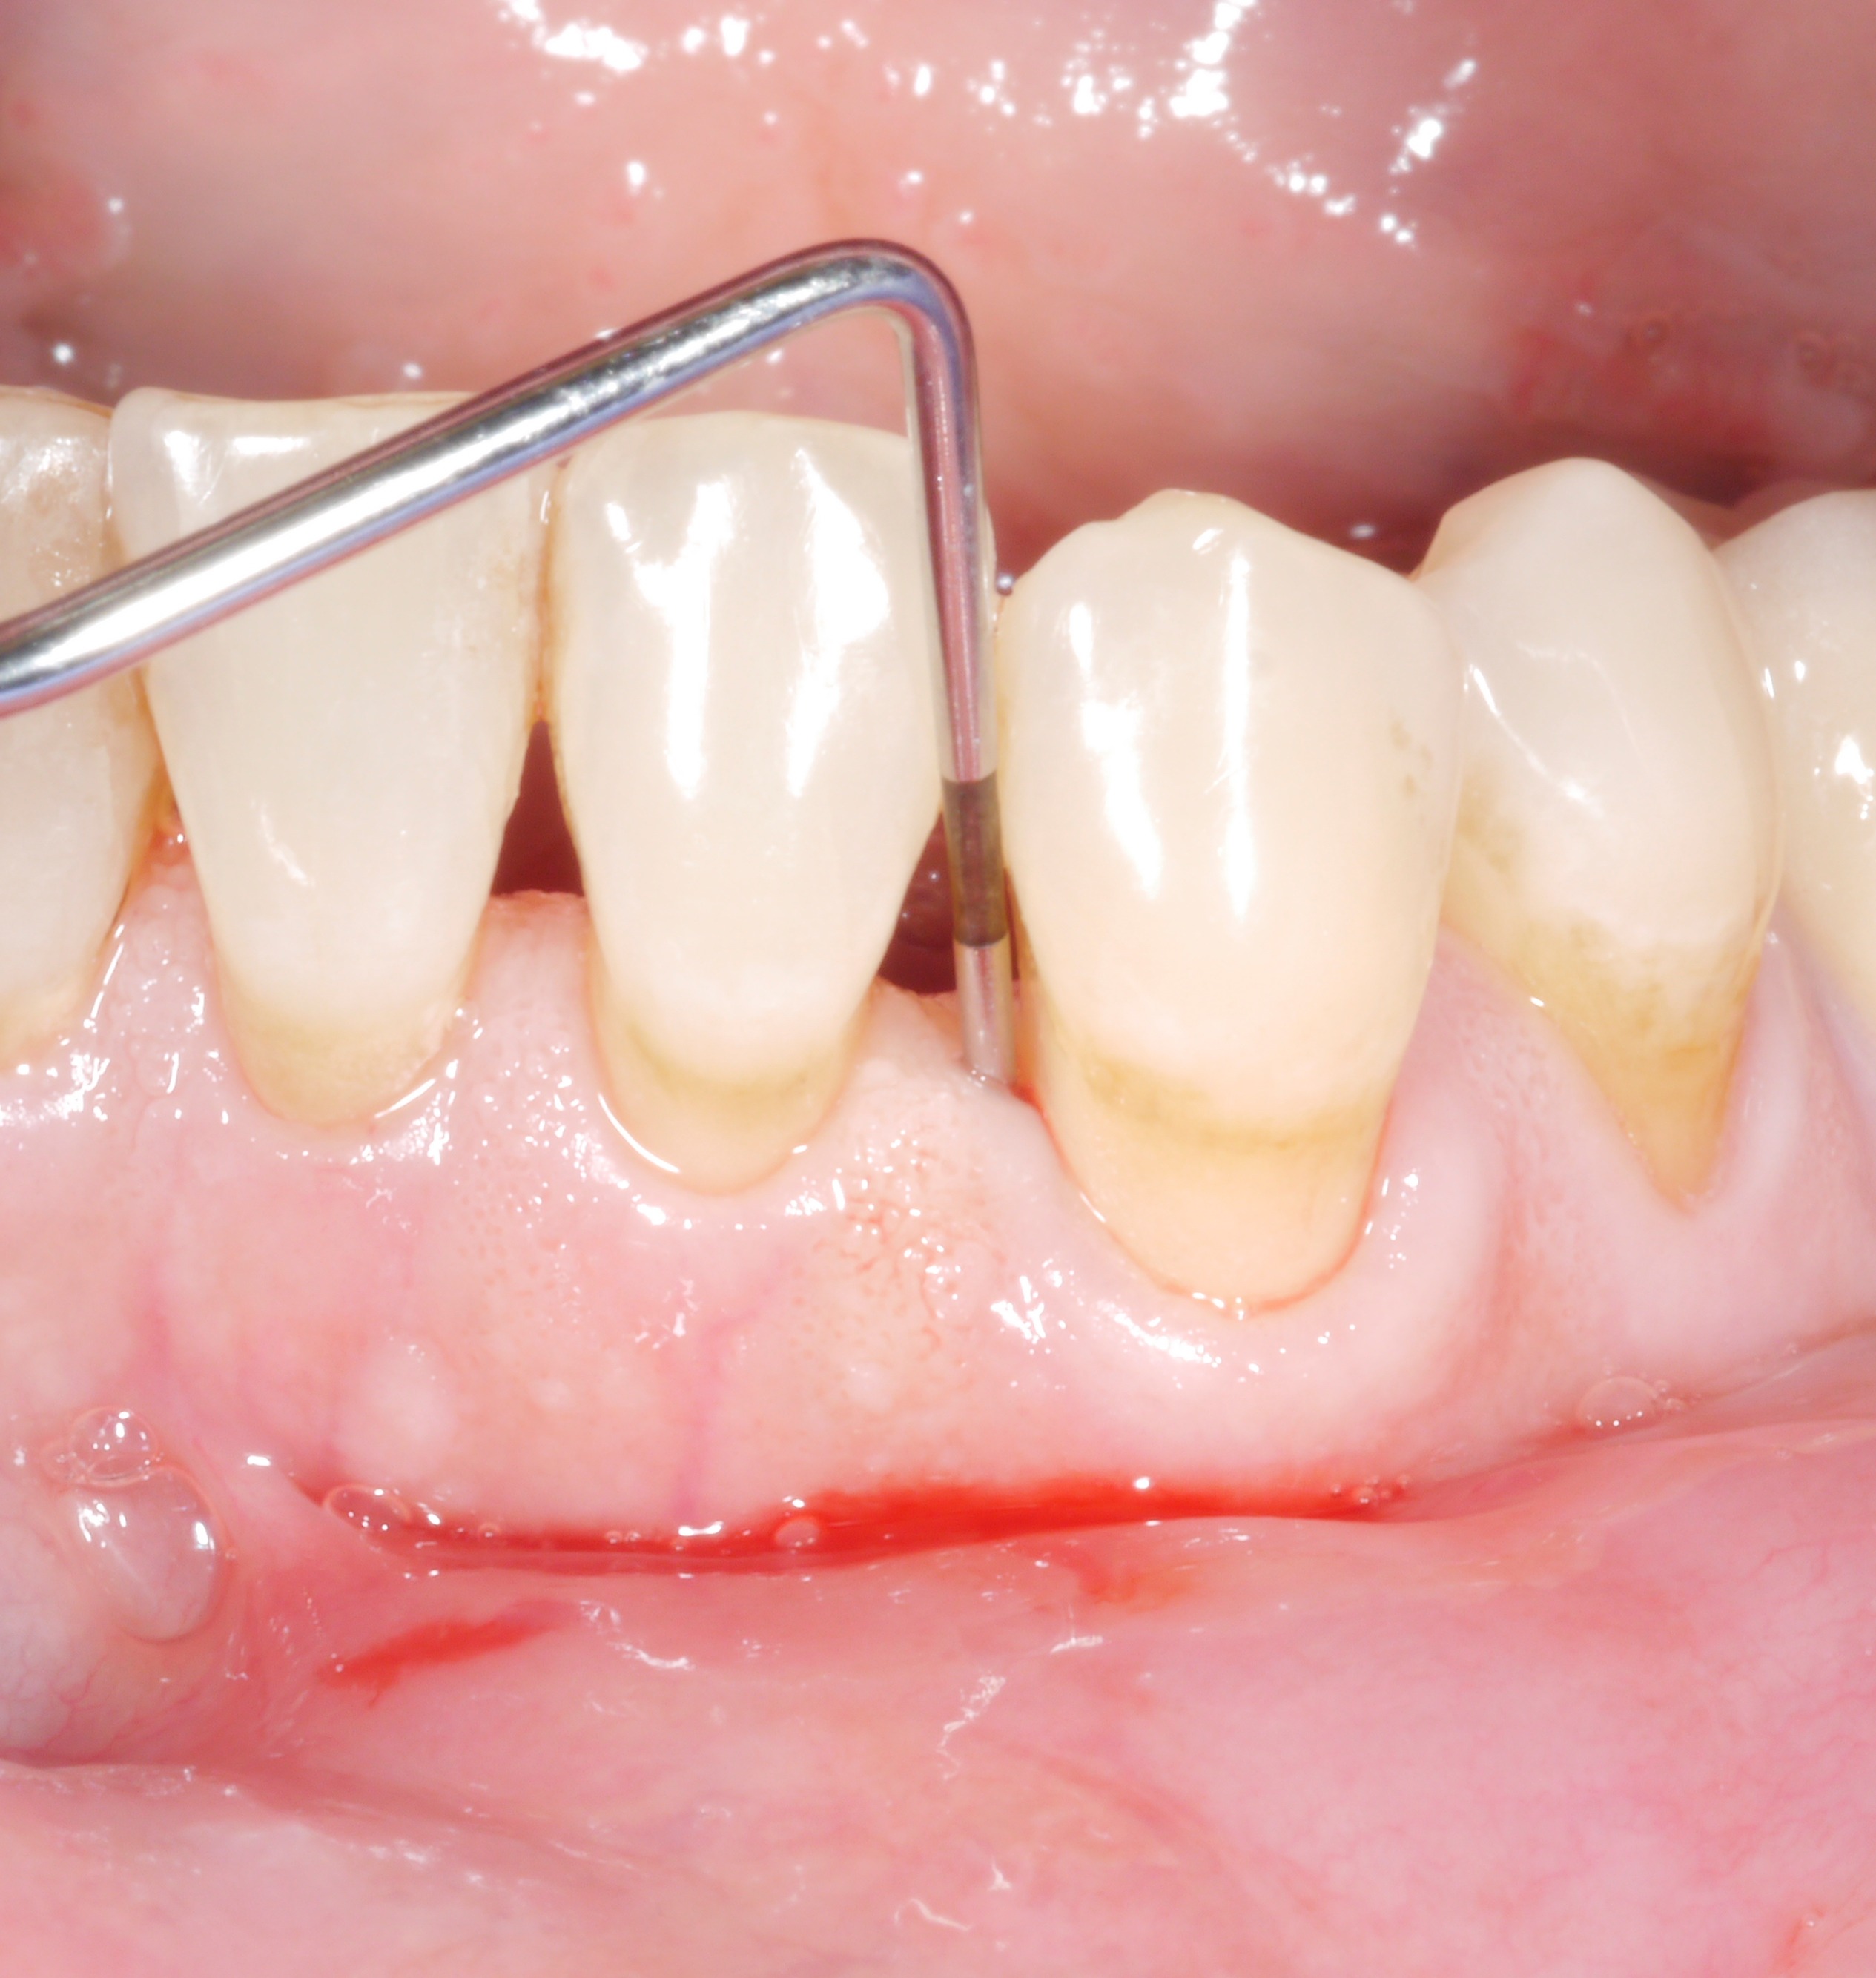

It is a situation we are all too familiar with: following the active phase of treatment, nearly all the patient’s teeth are now unaffected by increased pocket probing depths. However, there are still 1 or 2 places where the treatment goal has unfortunately not been achieved. The following thought might arise: “how bad can it be? A single pocket of 6 or 7 mm – surely that can’t make a big difference?

However, dentists should not rush to say they are content with residual pocket probing depths. This is because even individual residual pocket probing depths of more than 4 mm constitute a problem, as least in the longer term – both for the affected tooth and for the rest of the dentition.

The data from a Swiss study, which followed approximately 170 patients in maintenance therapy over an average period of 11 years, showed very clearly the problem posed by individual residual pocket probing depths:

• Individual residual pocket probing depths of 6 mm or more were a risk factor for a decline in general periodontal health and for tooth loss.

• Multiple residual pocket probing depths of 5 mm or more were also a risk factor for a decline in general periodontal health.

• Bleeding on probing doubled the risk of later tooth loss.

• The risk of tooth loss was almost 8 times higher for a pocket probing depth (PPD) of 5 mm, about 10 times higher for a PPD of 6 mm, and more than 60 times higher for a PPD of 7 mm!

Conclusion: The treatment goal should be to achieve pocket probing depths of 4 mm maximum and an absence of inflammation!